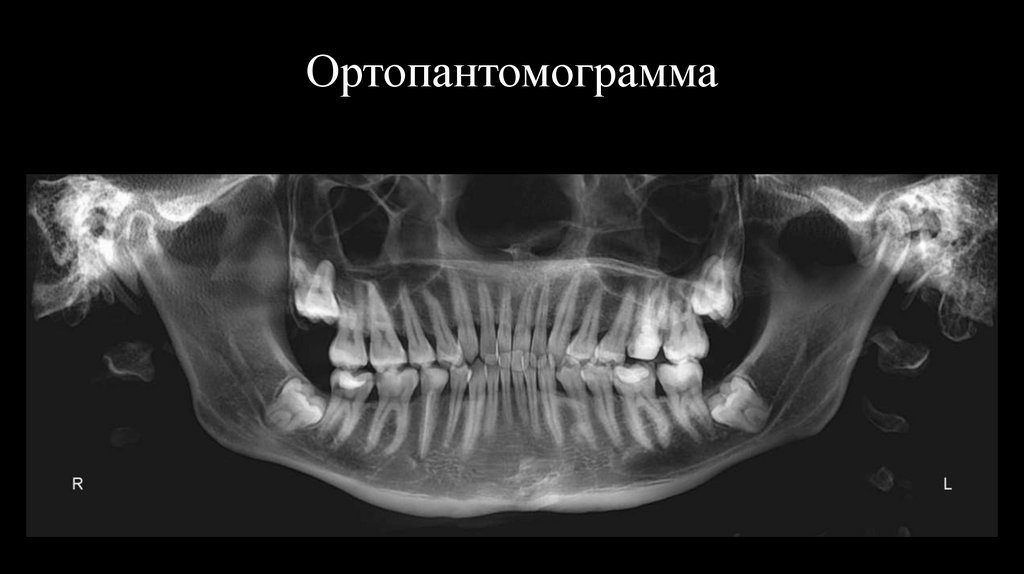

Ортопантомограмма

Выводы

11. Ортопантомограмма

12.

Объективно:

Контуры лица симметричны. Открывание рта свободное, безболезненное.

Девиация.

Пальпация жевательных мышц и ВНЧС безболезненна.

Хруст и щелчки в ВНЧС не аускультируется.

Слизистая оболочка розового цвета, не гиперемирована, не отчена, без

видимых патологических изменений. Уздечка верхней губы, нижней

губы и языка в норме.

Центральные линии не совпадают.

Аномалии положения зубов.

Классы по Энглю

по клыкам

по молярам

Справа

II

I

Слева